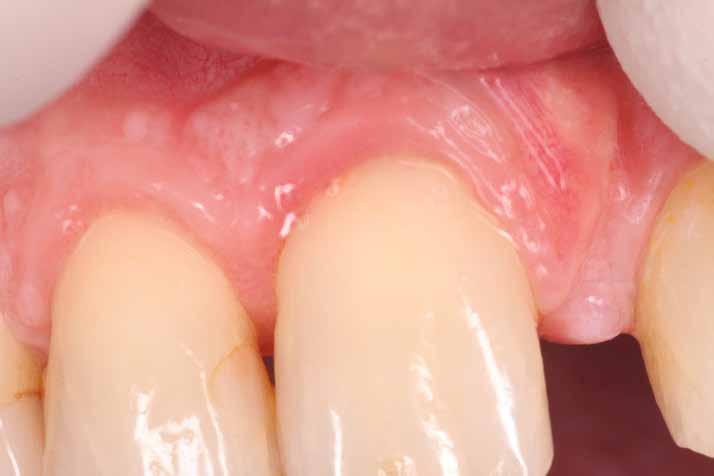

16. és 17. kép: Lebenyzárást követően befejeztük a fog gyökérkezelését. – 18. kép: 2 hónapos kontrollon a fog és az íny állapota is rendben.

a csatorna obliterálódását [14. kép]. Ezután megfelelő adhezív előkezelést követően kompozit tömőanyaggal restauráltuk az elváltozást (Essentia Universal, GC Europe) [15. kép]. Finírozást és alapos polírozást követően zártuk lebenyünket, majd újabb kofferdám izolálásban elvégeztük a fog gyökérkezelését [16. és 17. kép]. A kezelést követően páciensünk teljesen panaszmentes volt. Két hónapos kontrollon a fog teljesen ép, az íny tökéletes kitapadását tapasztaltuk [18. és 19. kép] Szondázási mélység a bukkális oldalon mindenhol 2 mm alatt volt.